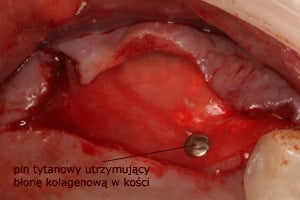

W metodzie z wypreparowaniem okna bocznego jesteśmy w stanie uzyskać nawet do 10mm nowej, świeżo utkanej tkanki kostnej, jednak przed wprowadzeniem implantu, wymagane jest odczekanie około 6-9 miesięcy w celu uzyskania przebudowanej, uformowanej nowej kości zdolnej do przyjęcia wszczepu. Niekiedy istnieje możliwość jednoczasowej implantacji wraz z zabiegiem podniesienia dna zatoki przy korzystnych relacjach ilości własnej kości do kości nowo tworzonej po zabiegu podniesienia dna zatoki. Postępowanie takie pozwala przyspieszyć zakończenie leczenia o okres późniejszego oczekiwania na osteointegrację implantu.

W każdej z metod, po odwarstwieniu błony Schneidera (błony śluzowej wyścielającej ściany zatoki), w wytworzoną przestrzeń wprowadzany jest materiał kościozastępczy będący zrębem dla powstawania nowej tkanki kostnej.